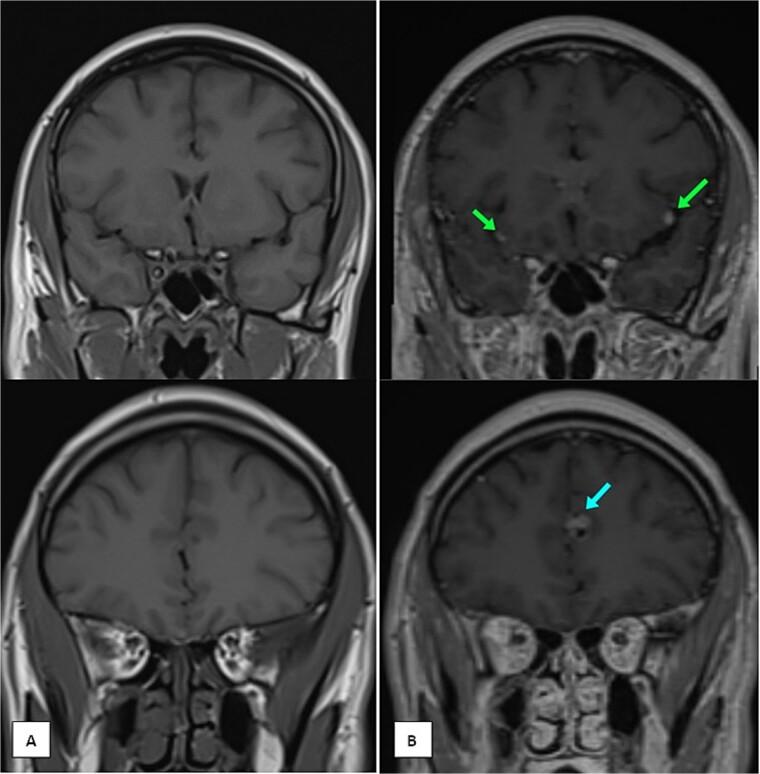

Nasopharyngeal carcinoma (NPC) is an epithelial malignancy commonly associated with Epstein-Barr virus infection. While bone, liver, and lung metastases are well-documented, central nervous system (CNS) involvement, particularly spinal and meningeal metastases, is extremely rare. We present a 41-year-old male with nasal obstruction and diplopia, diagnosed with locally advanced NPC. After treatment with chemotherapy and intensity-modulated radiotherapy, the patient achieved excellent locoregional control. However, months later, he developed persistent back pain, and imaging revealed metastatic deposits in the spine and meninges. Histopathological analysis confirmed metastatic NPC despite resolution of the primary tumor. The patient received palliative radiotherapy and intrathecal chemotherapy, but disease progression highlighted the aggressive nature and poor prognosis of CNS metastases in NPC. This case underscores the need for advanced imaging, histological confirmation, and tailored therapies in managing rare NPC metastases, with long-term follow-up and innovative therapies critical for improving outcomes in advanced disease.

鼻咽癌(NPC)是一种上皮性恶性肿瘤,通常与爱泼斯坦-巴尔病毒感染有关。虽然骨、肝和肺转移已有充分记录,但中枢神经系统(CNS)受累,尤其是脊髓和脑膜转移极为罕见。我们报告一名41岁男性,因鼻塞和复视而就诊,诊断为局部晚期鼻咽癌。经过化疗和调强放疗后,患者实现了良好的局部区域控制。然而,数月后,他出现持续背痛,影像学检查显示脊柱和脑膜有转移灶。尽管原发肿瘤已消退,但组织病理学分析证实为转移性鼻咽癌。患者接受了姑息性放疗和鞘内化疗,但疾病进展凸显了鼻咽癌中枢神经系统转移的侵袭性本质和不良预后。该病例强调了在处理罕见的鼻咽癌转移时,需要进行高级影像学检查、组织学确认和量身定制的治疗方法,长期随访和创新疗法对于改善晚期疾病的预后至关重要。